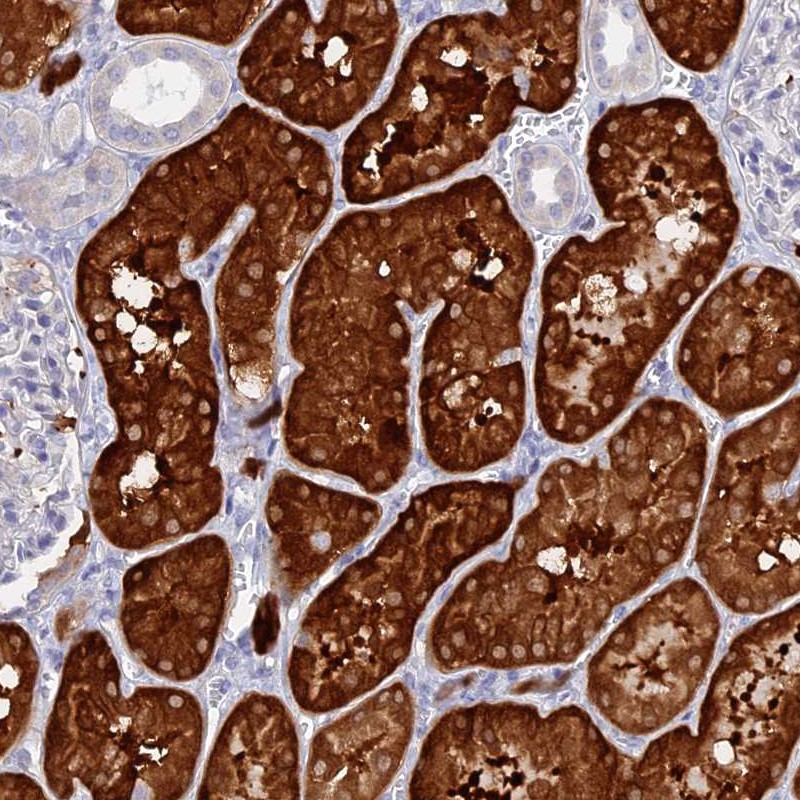

Immunohistochemical staining of human kidney shows strong cytoplasmic positivity in cells in tubules.